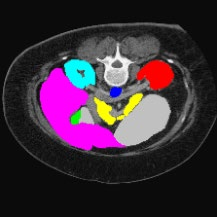

Transformers have made remarkable progress towards modeling long-range dependencies within the medical image analysis domain. However, current transformer-based models suffer from several disadvantages: (1) existing methods fail to capture the important features of the images due to the naive tokenization scheme; (2) the models suffer from information loss because they only consider single-scale feature representations; and (3) the segmentation label maps generated by the models are not accurate enough without considering rich semantic contexts and anatomical textures. In this work, we present CASTformer, a novel type of generative adversarial transformers, for 2D medical image segmentation. First, we take advantage of the pyramid structure to construct multi-scale representations and handle multi-scale variations. We then design a novel class-aware transformer module to better learn the discriminative regions of objects with semantic structures. Lastly, we utilize an adversarial training strategy that boosts segmentation accuracy and correspondingly allows a transformer-based discriminator to capture high-level semantically correlated contents and low-level anatomical features. Our experiments demonstrate that CASTformer dramatically outperforms previous state-of-the-art transformer-based approaches on three benchmarks, obtaining 2.54%-5.88% absolute improvements in Dice over previous models. Further qualitative experiments provide a more detailed picture of the model's inner workings, shed light on the challenges in improved transparency, and demonstrate that transfer learning can greatly improve performance and reduce the size of medical image datasets in training, making CASTformer a strong starting point for downstream medical image analysis tasks.